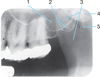

1.

Outline of nose

Identify the following Radiolucent Anatomical Landmarks

Incisive Foramen

(exit of nasopalatine nerve, appears ovoid between

roots of maxillary central incisors in radiographs)

3

Identify the following Radiolucent Anatomical Landmarks

(smooth depression located between lateral and canine, appearance varies in area between maxillary canines and lateral incisors)

Lateral fossa

4

Identify the following Radiolucent Anatomical Landmarks

(pear shaped compartment of bone located superior to maxilla and divided by nasal septum, appears as a large area above maxillary incisors in radiographs)

Nasal fossa

5

Identify the following Radiopaque Anatomical Landmarks

(vertical bony wall dividing nasal cavity, appears as a vertical partition, and may be superimposed over median palatine suture)

Nasal Septum

6.

Identify the following:

Border of nasal fossa

7

Identify the following Radiopaque Anatomical Landmarks

(sharp projection located at the anterior and inferior portion of nasal cavity, appears v-shaped, intersection of floor of nasal cavity and septum)

Anterior nasal spine

8

Identify the following Radiolucent Anatomical Landmarks

(immovable joint between two palatine processes of maxilla, appears as a

thin line between maxillary central incisors in radiographs)

Median palatine suture